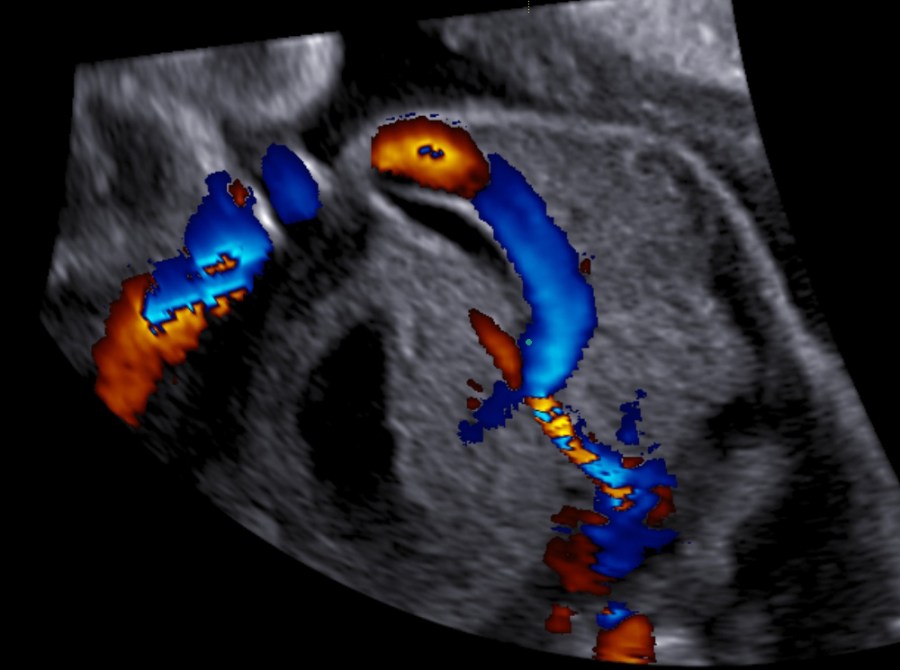

- Doppler velocimetry of the middle cerebral artery to exclude fetal anemia

Causal therapy should be attempted. Gestational diabetes should be controlled. Fetal anemia can be treated with transfusion and fetal arrhythmia can be handled with antiarrhythmic agents given to the mother. Naturally, some of the causes that have already been mentioned cannot be treated during pregnancy, meaning that some patients could have persisting polyhydramnios.